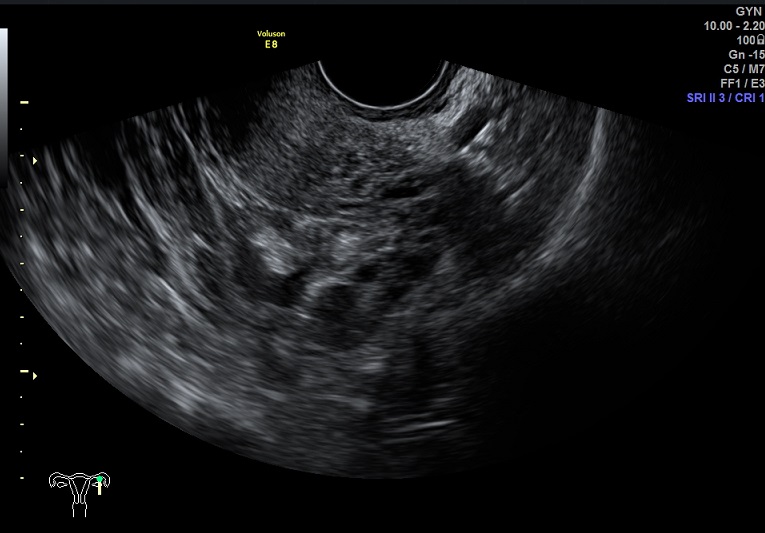

右卵巢黄体